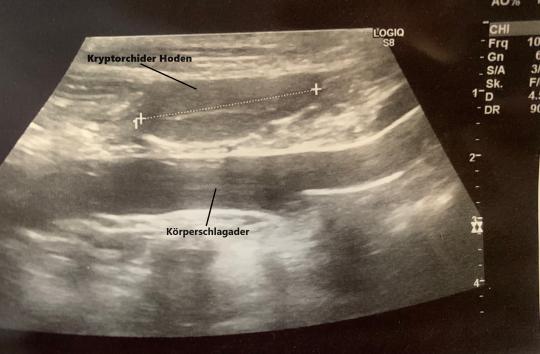

In Narkose ist in der Leistengegend kein Hoden tastbar. Im Ultraschall ist ersichtlich, dass das gesuchte Organ im hinteren Bereich der Bauchhöhle liegt. Nach Rücksprache mit den Besitzern wird eine Entfernung mittels Knopfloch-Chirurgie (laparoskopische Chirurgie) in Angriff genommen.

Bauchhöhle in das Hodensäckchen des Welpen. So kann gewährleistet werden, dass sie kühlere Temperaturen als in der Bauchhöhle vorfinden, was für die Spermienproduktion notwendig sind. Bleibt der Hoden auf seinem Weg von der Bauchhöhle in den Hodensack irgendwo "stecken", spricht man von Hodenhochstand oder Kryptorchismus (griechisch "krypto" = verborgen, "Orchis" = Hoden). Je nach Lokalisation spricht man von inguinalem (im Leistenkanal) oder abdominalen (in der Bauchhöhle) Kryptorchismus. Kryptorchide Hoden stellen ein Gesundheitsrisiko dar, weil sie gegenüber einem normalen Hoden ein erhöhtes Krebsrisiko aufweisen und sich eine Hodentorsion (Verdrehen des Hodens) bilden kann. Entsprechend sollten sie entfernt werden. Da der Hodenhochstand vererbt werden kann, sollte mit betroffenen Rüden nicht gezüchtet werden. Die Spermienproduktion (nicht aber die Testosteronbildung) in einem kryptorchiden Hoden ist stark vermindert oder gar ganz unmöglich, entsprechend ist er auch viel kleiner als ein normaler Hoden. Die laparoskopische Entfernung hat gegenüber der konventionellen Methode den Vorteil, dass eine viel kleinere Öffnung in die Bauchhöhle geschnitten werden muss.